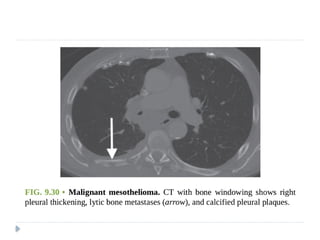

MALIGNANT MESOTHELIOMA

⚫ Highly malignant and locally aggressive tumor

⚫ 6th or 7th decade of life

⚫ Associated with asbestos exposure, with an average latency of

35-40 years for its development.

⚫ Other predisposing factors :

⚫ Radiation therapy

⚫ Tuberculosis

⚫ Chronic empyema

On imaging :

⚫ Diffuse nodular pleural thickening – pleura along the

intercostal spaces, costophrenic angles and lung apices

are involved.

⚫ Pleural plaques (latent period of formation is 20yrs; strong

indicator of asbestos exposure): usually seen adjacent to ribs.

Involving sixth to ninth rib. These themselves are not

premalignant

⚫ Pleural effusion

⚫ Calcifications may be seen along diaphragmatic pleura.